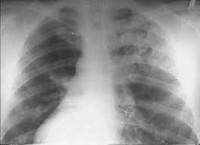

Наиболее чувствительным и специфичным методом диагностики синдрома Гудпасчера служит определение антител к базальной мембране клубочков (Anti-GBM) с помощью ИФА или РИА. На рентгенограммах легких выявляются множественные очаговые тени. Морфологическое подтверждение синдрома Гудпасчера основывается на данных биопсии легких и почек. Вспомогательное значение имеют результаты инструментальной диагностики: спирометрии, УЗИ почек, ЭКГ, ЭхоКГ.